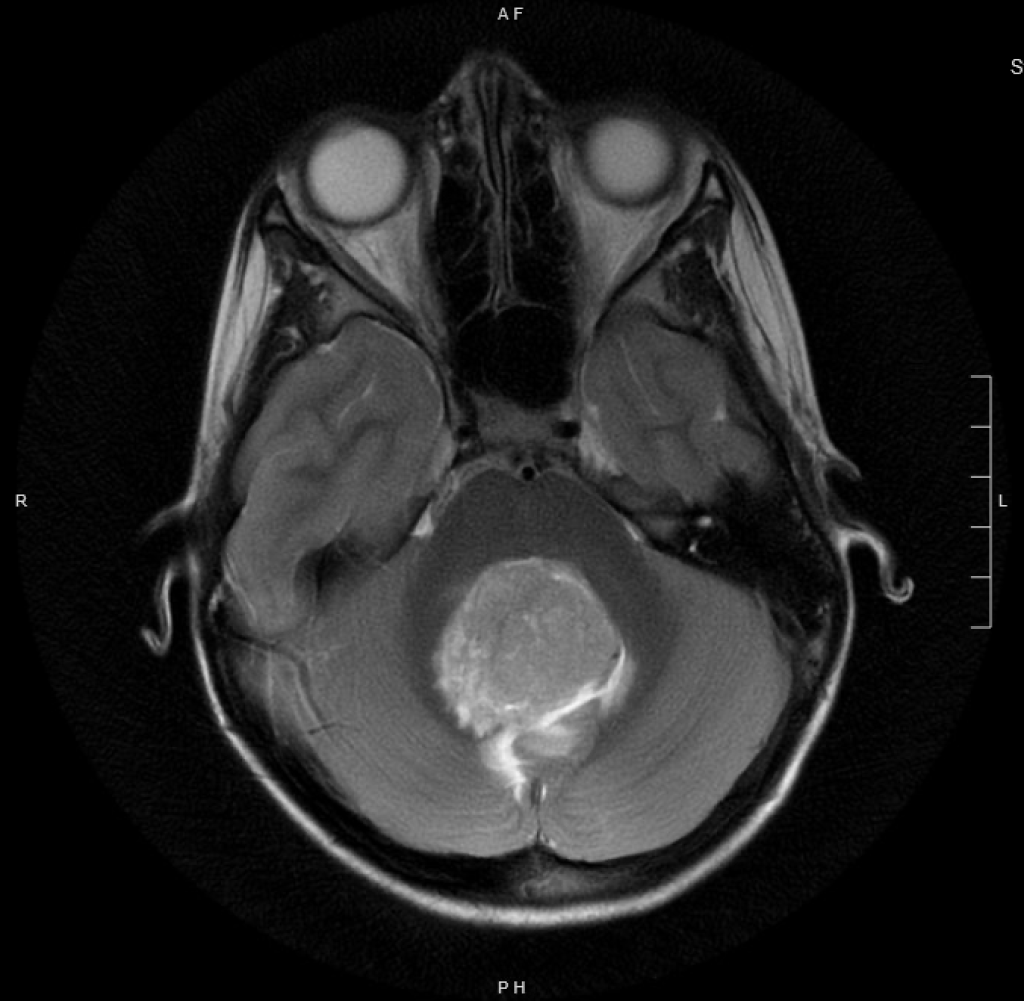

Brain tumors are the most common solid tumors affecting children and adolescents. Medulloblastoma and ependymoma tumors are two common pediatric brain tumors that require radiation therapy for cure. Both tumors occur in young children, the median age being 5 years or less. All medulloblastomas and ~60% of ependymomas arise in the posterior fossa. Medulloblastoma is a tumor that commonly metastasizes through the cerebrospinal fluid and necessitates craniospinal irradiation (CSI) in children 3 years and older, even when the disease is localized. Typical radiation doses for medulloblastoma are 18-36 Gy CSI, followed by a boost to the tumor bed to 54 Gy. Treatment for localized ependymoma requires 50.4-59.4 Gy radiation to the tumor bed only. While radiation is an essential part of curative treatment for these tumors, radiation to the developing brain can also result in adverse late effects.